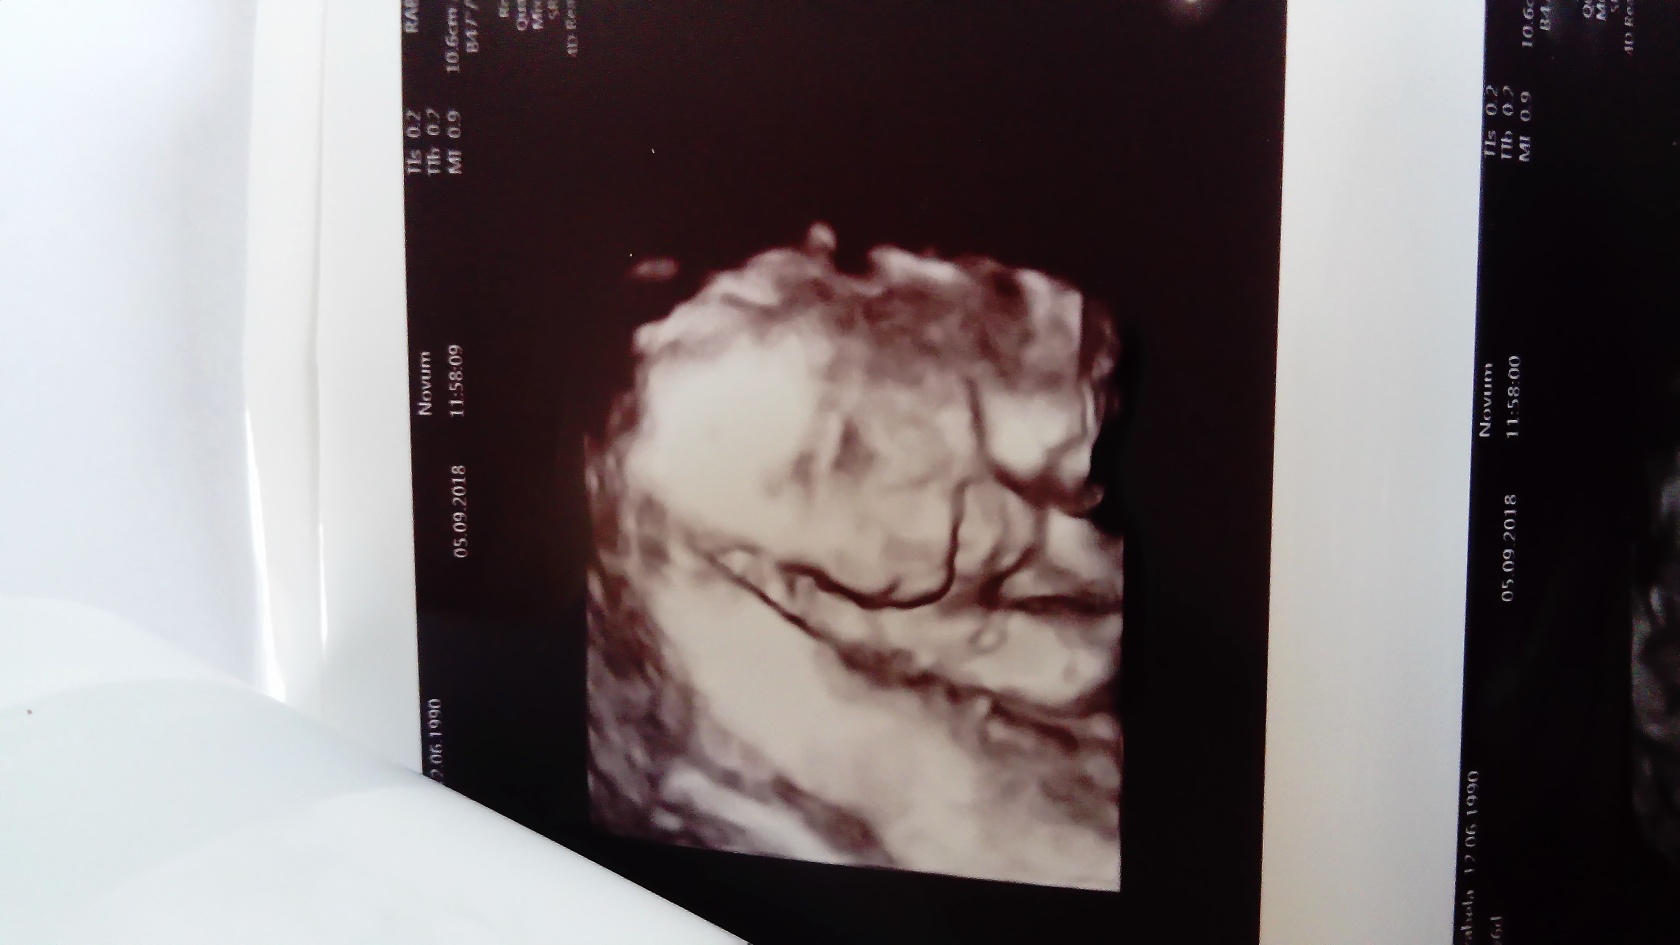

Dziękuję dziewczyny, nie mogłam się na patrzeć na małego, choć spał podczas badania mam jedno zdjecie na którym sie uśmiecha, nie samowitę jak można już kochać takie maleństwo.

SynuśWiadomość wyedytowana przez autora: 5 września 2018, 20:32

Było w cenie usg, nawet nic nie mówiłam, doktor sama powiedziała że nagra badania a poźniej film dla nas w 3D.z tym że u nas w klinice badania czy to prenatalne czy połówkowe 300zl.ale chodze tam bo mam do nich zaufanie.